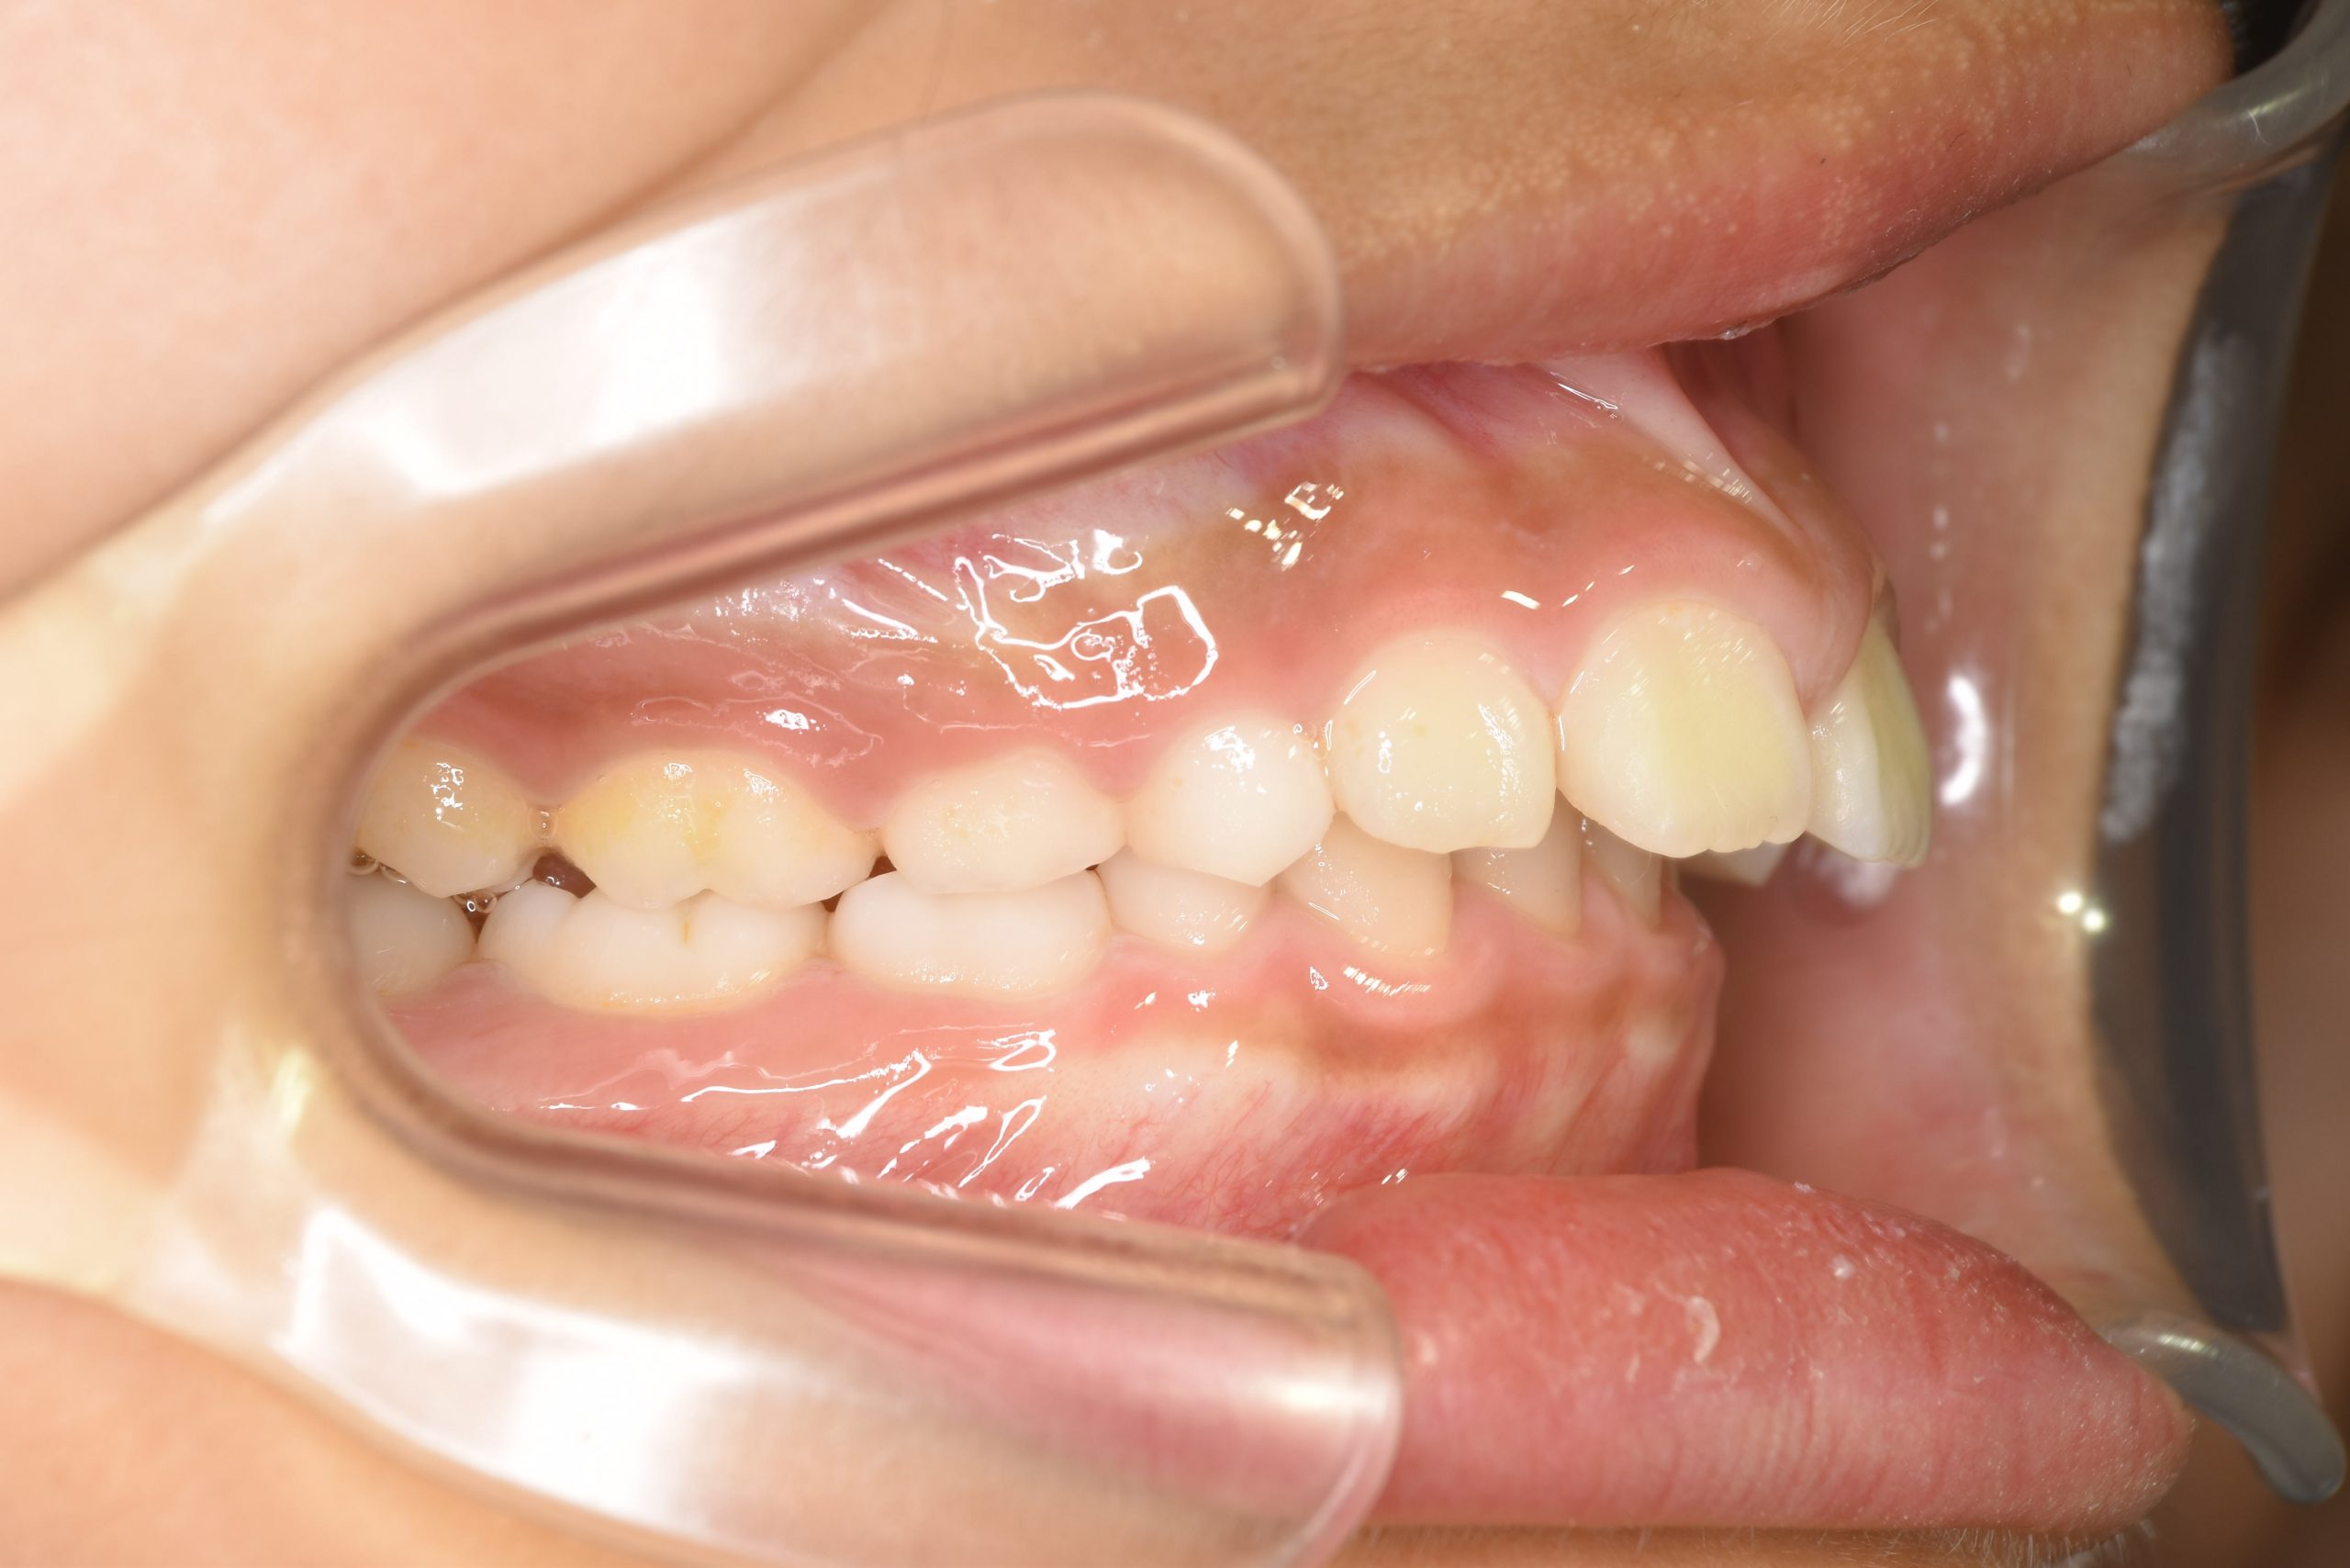

アフター

子どもの矯正治療|症例_547

施術内容 上顎急速拡大装置と下顎リンガルアーチを用いて上下顎骨を拡大した。

その後マウスピース型矯正装置で歯牙を配列し良好な咬合を獲得した。

治癒期間 2年10か月